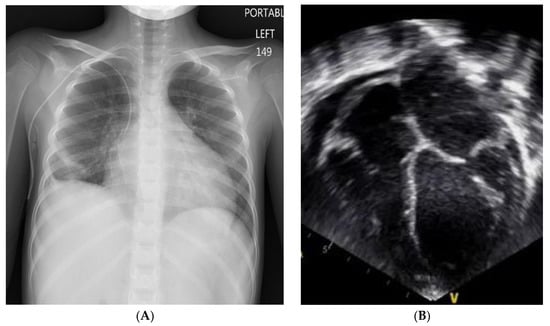

- Case 1: